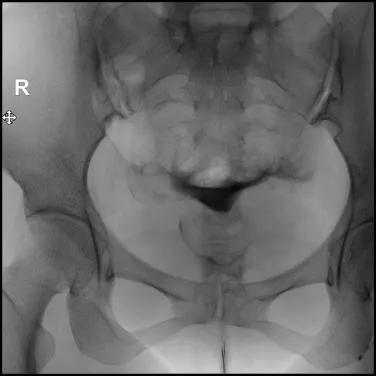

9.在注入对比剂后的20分钟或24小时再拍一张弥散片,观察对比剂在盆腔的弥散情况,分析宫颈、子宫、输卵管的形态特征;

充盈片

弥散片